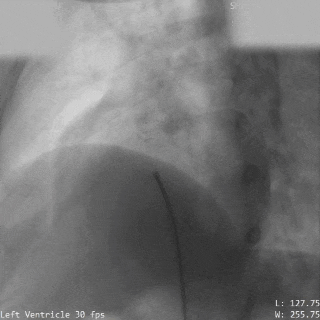

封堵器形态良好,基本无残余分流

本例患者于外院体检时发现心脏异常,升主动脉造影初步提示破口约8mm。由于患者抵抗力较低,如植入镍钛合金封堵器,术后需终身预防感染性心内膜炎,因此外院曾建议行外科手术修补。为进一步明确破口情况,术前团队对其进行了详尽的超声及造影评估,确认破口直径约为5mm,血流通向右房。考虑到破口位置靠近瓣膜,且可降解封堵器能够实现生理性修复,术后不留异物,无需终身预防感染性心内膜炎,本次手术最终选用ABFDQ-II 10全降解封堵器进行封堵。该封堵器材料柔韧,植入后可自适应周围结构及组织运动,不易影响或磨损瓣膜功能。术中释放后封堵器形态稳定,瓣上造影显示基本无残余分流,主动脉瓣启闭正常,手术取得圆满成功。术后1天超声复查提示瓦氏窦瘤封堵效果良好,封堵器位置及功能正常,患者恢复顺利,已康复出院。